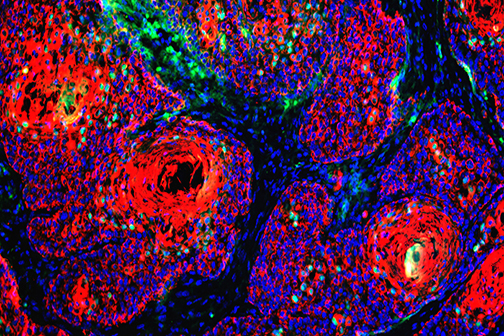

LSU Health Research Suggests A New Approach For Treatment-Resistant Breast Cancers

A collaborative study between LSU Health New Orleans School of Medicine, the University of Rochester and Cellestia Biotech AG, a biopharmaceutical company headquartered in Basel, Switzerland, provides compelling evidence that combining an investigational oral drug with standard-of-care medications reverts hormone resistance and increases Rx effectiveness in experimental models of estrogen-receptor positive (ER+) and triple-negative breast cancers (TNBC), respectively. More

LSU Health Research Finds New Drug Target for Triple-Negative Breast Cancer

Research led by Dr. Suresh Alahari, Professor of Biochemistry at LSU Health New Orleans’ Schools of Medicine and Graduate Studies, reports a combination of a novel small inhibitory molecule and an FDA-approved chemotherapy drug suppresses the growth of triple-negative breast cancer cells synergistically. More

Study Reports Blocking Key Enzyme Boosts Anti-Cancer T-Cell Responses and Resistance to Immunosuppression

A study led by LSU Health New Orleans cancer researchers describes a novel therapeutic strategy to overcome tumor-induced immunosuppression. For the first time, the research team identified a critical immunosuppressive pathway and a promising approach to intervene, protecting the ability of T-cells to attack cancer cells. Results are published in Frontiers in Immunology. More